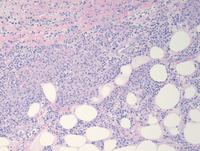

HE images of Lymphoepithelioid variant (Lennert's lymphoma)

Low and high power images showing diffuse infiltrate rich in histiocytes and scattered small lymphocytes that are percolating the surrounding adipose tissue and in between the histiocytic infiltrate.